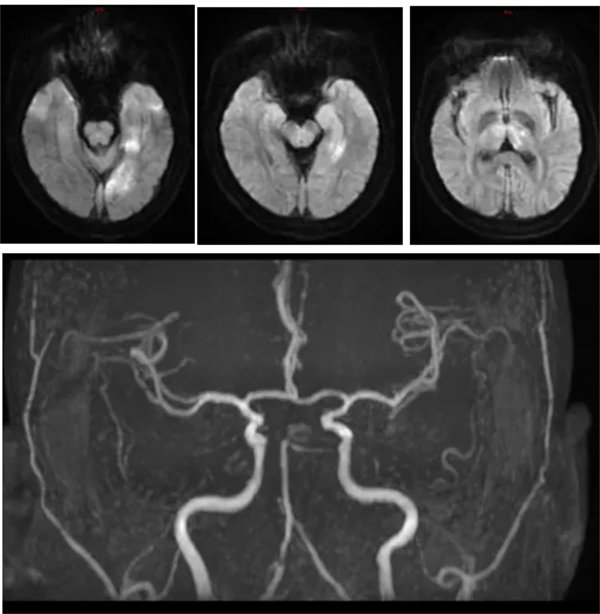

近日,42歲的張先生因突發(fā)頭暈、右手無(wú)力、視物模糊10小時(shí),意識(shí)不清10分鐘,被家屬發(fā)現(xiàn)后緊急送至我院急診科,考慮腦卒中收入神經(jīng)內(nèi)三科進(jìn)一步治療,到達(dá)科室后患者已神志不清,且伴有呼吸淺快,大小便不能自控。NIHSS評(píng)分35分,mrs評(píng)分4分;行頭顱DWI提示左側(cè)顳枕葉、左側(cè)丘腦急性腦梗死;顱腦MRA提示右側(cè)大腦后及小腦上動(dòng)脈未見(jiàn)顯影,左側(cè)大腦后動(dòng)脈P1段明顯變細(xì),遠(yuǎn)端閉塞。